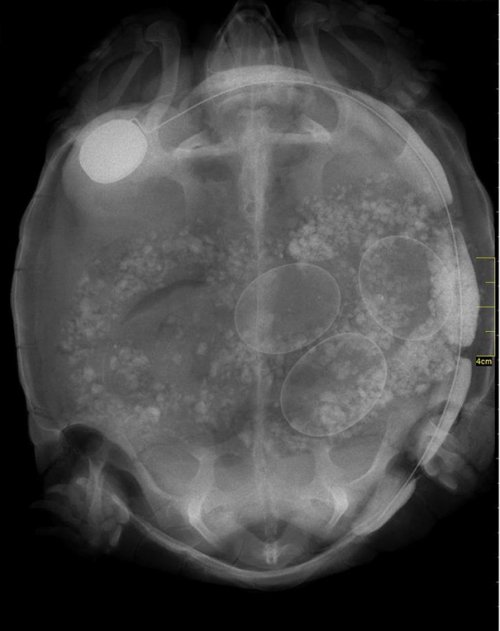

Итак, как выглядят рентгеновские снимки беременных животных:

черепаха